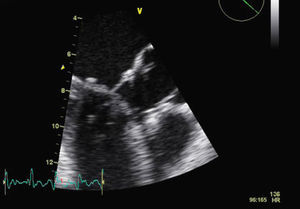

Six weeks after her initial admission to our department, the patient was seen at the outpatient clinic; she was hemodynamically stable, in good general health and with no signs of heart failure. The report from the surgical center, where she had remained for three weeks, revealed that surgical reintervention had not been necessary. TTE at discharge showed significant improvement in echocardiographic parameters (mild mitral regurgitation and no LVOT obstruction by the mitral anterior leaflet). Repeat TTE a week after reassessment, with optimized HR, revealed good MV function (mild regurgitation), with no LVOT obstruction (Figures 4 and 5).